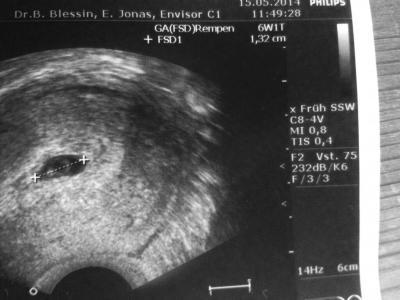

mein Mini ist jetzt 2mm und die Fruchthöhle bei 1,32 cm (laut US 6+1) und ab heute bin ich in der 7. SSW